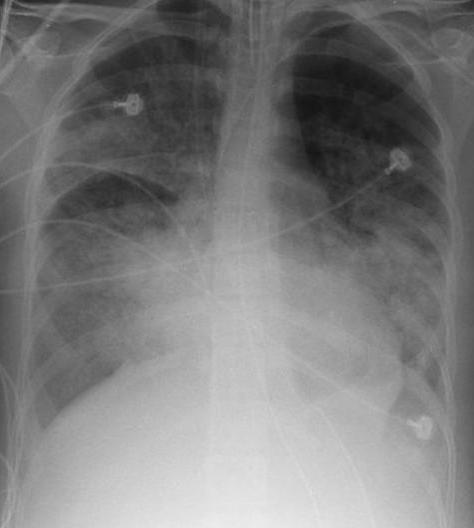

- Insuficiența respiratorie reprezintă o afectare a schimbului gazos, cu impact imediat asupra oxigenării și eliminării dioxidului de carbon.

- Cauzele pot fi diverse – de la afecțiuni pulmonare acute sau cronice la tulburări neuromusculare sau dezechilibre sistemice – iar contextul clinic influențează evoluția.

- Evaluarea integrată și intervenția timpurie, orientate spre restabilirea funcției respiratorii și tratarea cauzei subiacente, sunt esențiale pentru îmbunătățirea rezultatelor.

- Prognosticul variază și depinde de severitate, comorbidități și răspunsul la tratament; monitorizarea și prevenția riscurilor complementare rămân prioritare.